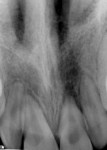

At presentation (Figure 1 through Figure 4), the patient was symptomatic with a dull ache. Teeth Nos. 8 and 9 were repositioned incorrectly, with tooth No. 9 being severely malpositioned. Upon examination, the patient was afebrile and alert and oriented times three. He stated that he did not lose consciousness at the time of the trauma. The patient’s vital signs were determined and considered normal. The patient had no history of significant medical disease, denied all medications, and had no known drug or food allergies. His review of systems was noncontributory for systemic disease. The patient’s head-and-neck examination exhibited no signs of facial fracture. A small laceration of his upper lip in association with tooth No. 9 was healing well. Teeth Nos. 8 and 9 were malpositioned, with tooth No. 9 being severely extruded. The remainder of his head-and-neck examination was unremarkable.

Teeth Nos. 8 and 9 were tender to percussion and palpation. Teeth Nos. 8 and 9 were nonresponsive to cold testing (Frigi-dent™, Ellman International, www.ellman.com). Teeth Nos. 8 and 10 were +1 mobile, while tooth No. 9 was +3 mobile. The gingival tissue around tooth No. 9 was erythematous. Periodontal probing depths were 3 mm to 4 mm generalized for all teeth except tooth No. 9, whose probing depths were 6 mm to 8 mm. Upon radiographic examination, teeth Nos. 8, 9, and 10 had widened periodontal ligament spaces. No other pathology was noted. The remainder of the examination was unremarkable.